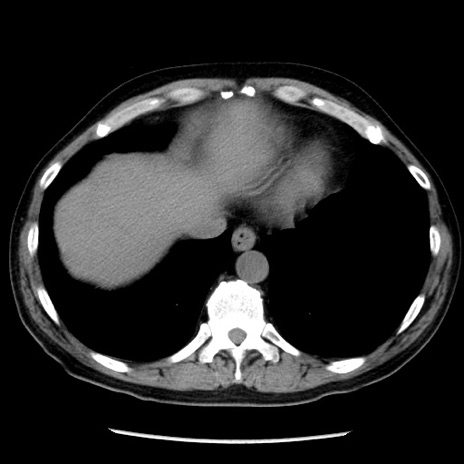

症例29(横断像)

【症例】40歳代男性

【現病歴】2日前から胃痛あり。徐々に周期的な激痛に変化した。本日になっても激痛があるため受診。

【身体所見】意識清明、BT 38-39℃台あり、腹部:膨満、やや硬、右下腹部に圧痛あり。

【データ】WBC 8500、CRP 23.26